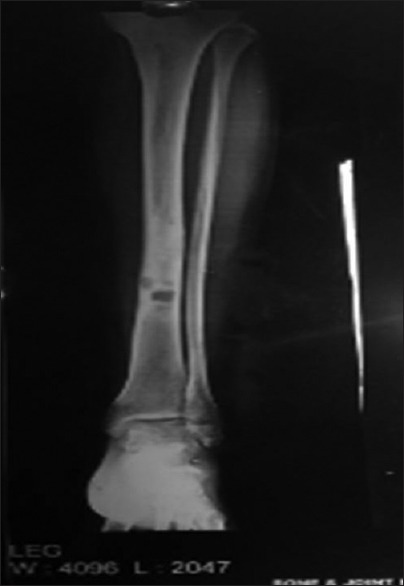

Further evaluation was carried out with imaging of chest and abdomen, along with imaging of referable sites. Contrast-enhanced computed tomography (CECT) chest and abdomen was carried out in all patients, revealing right hilar mass in 66% of patients, left hilar mass in 22%-of patients, and 12%-had right peripheral lung mass. Superior vena cava (SVC) partial or complete occlusion was seen in 33%; right-sided plural effusion, ascites, and liver metastasis was seen in 11%-each [Figures [Figures11 and and2].2]. Bronchoscopy revealed intrabronchial pathology and clinched the diagnosis in 88% of patients; rest of patients needed computed tomography (CT)-guided biopsy of lung for getting histological diagnosis. Lung biopsy was positive for napsin, cytokeratin (CK) 5/6, and negative for synaptophysin and thyroid transcription factor 1 [Figure 3]. Bone scan was positive in two patients with one uptake in iliac bone and other in Tibia [Figure 4 of X-ray Tibia]. CECT of muscle metastasis sites was done and biopsy was carried out in each patient [Figure 5]. Distribution of metastasis was unique, 66%-patients had pelvic skeletal muscle involvement, 22%-had thigh muscle, and 11%-had lower paraspinal muscle metastasis.

| Figure 4:Bone metastases in Tibia with sclerosis around lytic lesion